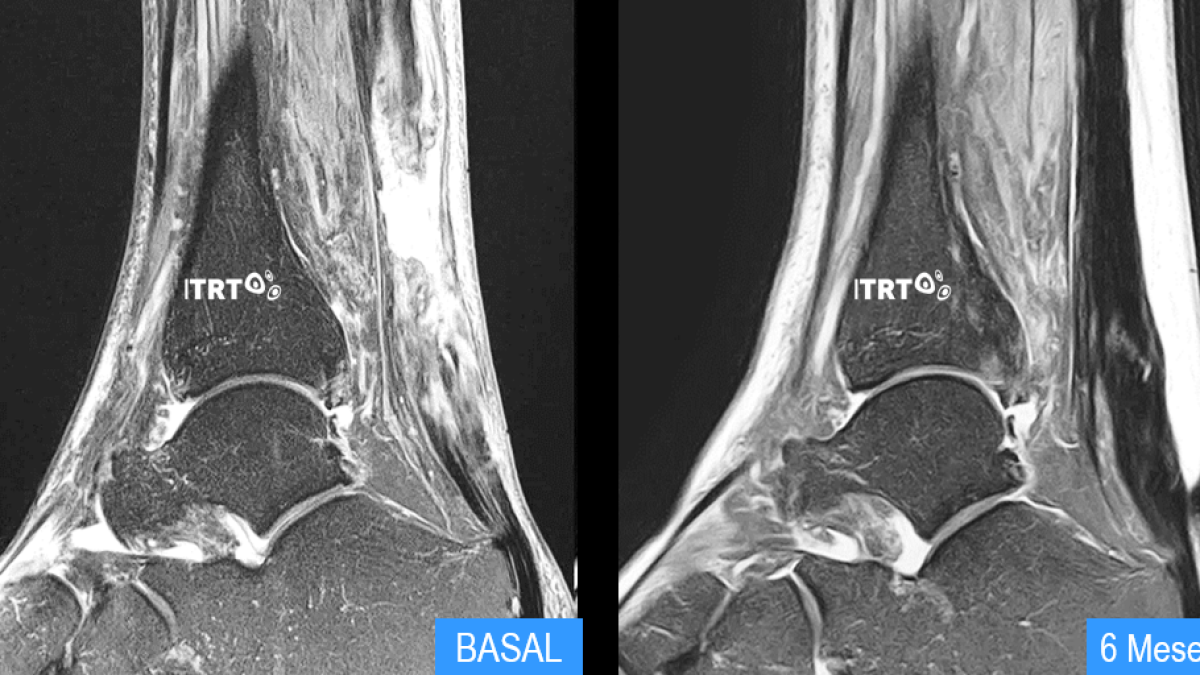

Un ensayo clínico a doce meses hecho por el Instituto de Terapia Regenerativa Tisular (ITRT) ha demostrado que las células madre mesenquimáticas cultivadas son capaces de regenerar tendón, incluso en lesiones crónicas. La investigación se ha publicado en 'Orthopaedic Journal of Sports Medicine' y supone un cambio de paradigma en traumatología y medicina del deporte, ya que se consideraba imposible regenerar este tejido. Se abre ahora una nueva opción para casos hasta ahora incurables. El ITRT ha obtenido este resultado después de una investigación de 20 años que ha dado lugar a un protocolo específico con células madre cultivadas que la Agencia Española del Medicamento ya ha autorizado para tratar otros tejidos, como el cartílago, el huesoo el disco vertebral.

Los resultados del ensayo muestran un grado de regeneración sin precedentes en el 100% de los pacientes, con disminución del dolor y una reincorporación a la práctica deportiva al cabo de dos meses. En el ensayo clínico, controlado, aleatorizado y evaluado con doble cec, han participado 20 pacientes de entre 18 y 48 años afectados por una lesión crónica de más de 3 milímetros del tendón rotuliano. Todos ellos practicaban deporte de manera habitual y ninguno había respondido a los tratamientos conservadores habituales.

Los pacientes del primer grupo mostraron una regeneración evidente del tendón inmediata, mientras que los del segundo sólo consiguieron reducir las molestias de dolor, sin que el tendón evolucionara, de manera que este segundo grupo pasó a tratarse con las células madre al cabo de seis meses. Al cabo de doce meses de recibir el tratamiento, todos los pacientes mostraron una regeneración de tendón del 100%.